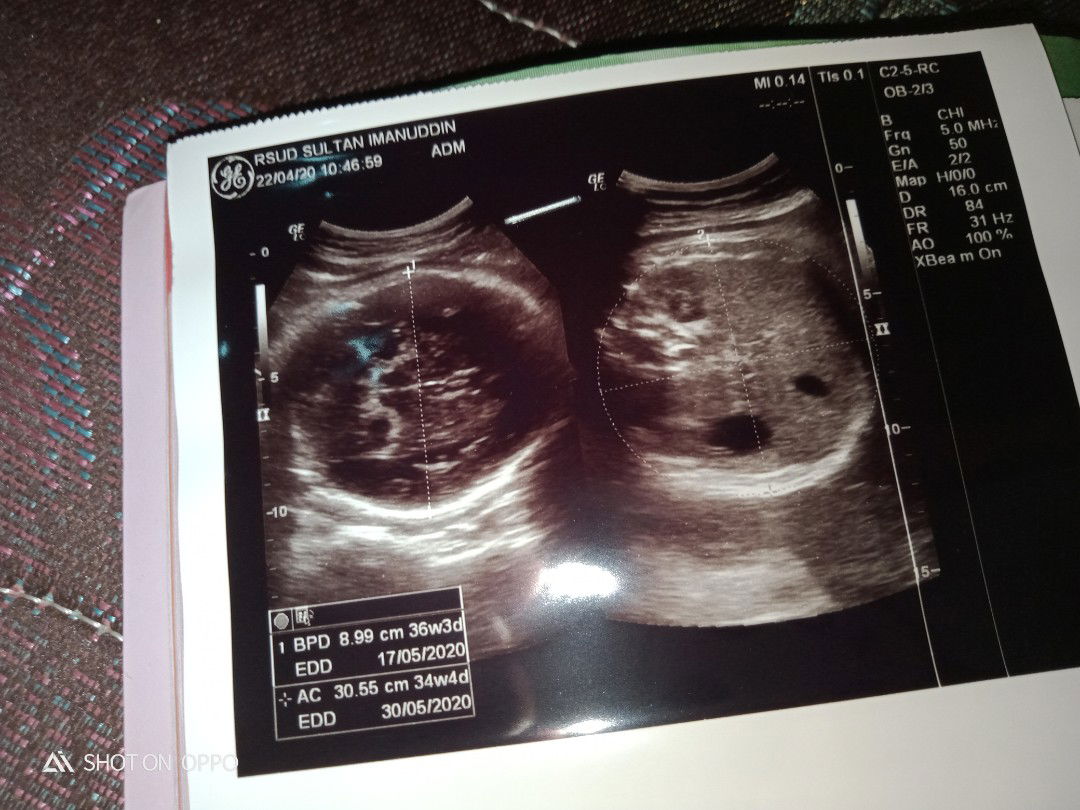

Usg ke 2 semua nya sehat hasil nya jenis kelamin cewek , tinggal menunggu waktu dan nunggu baby lahir,sehat sehat sayang ?